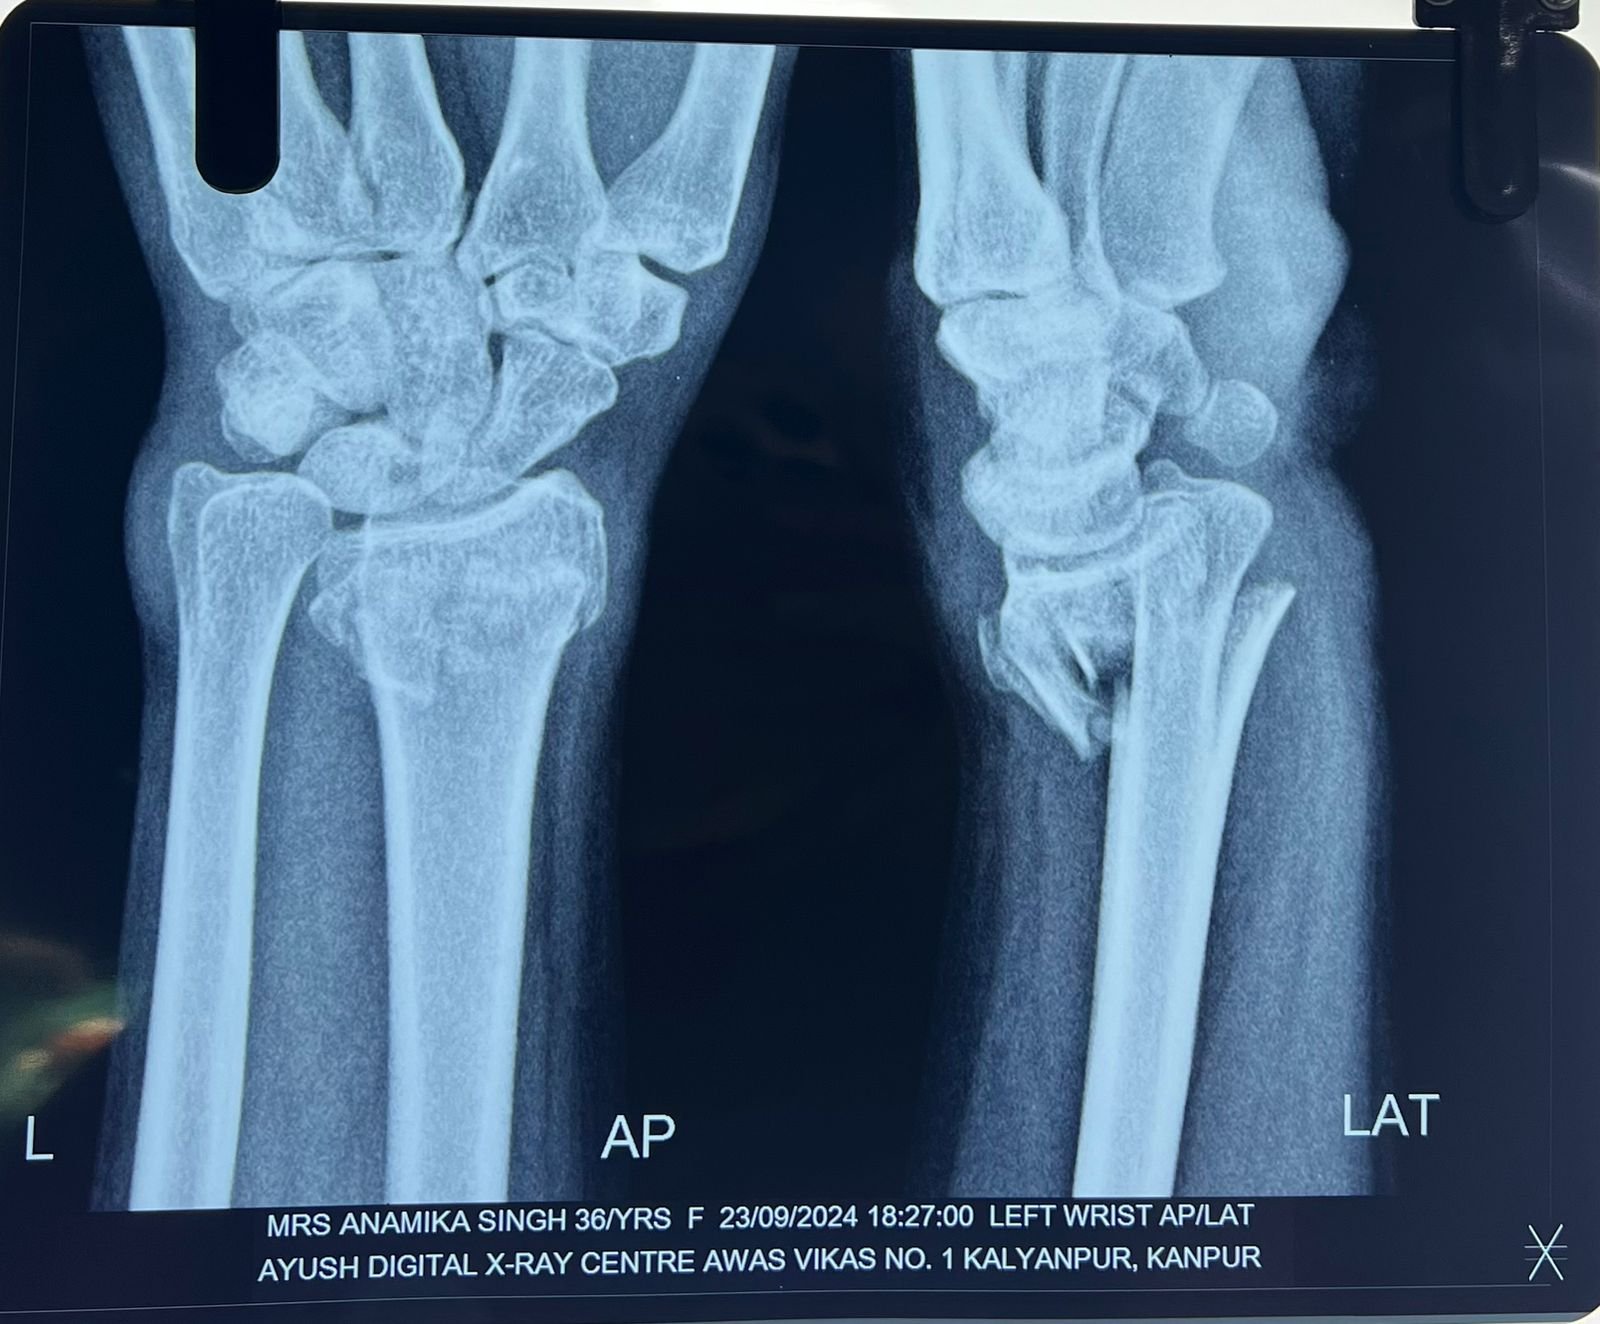

Heal fracture pre & postop | Clavicle fracture pre &

postop | Congenital foot deformity pre & post